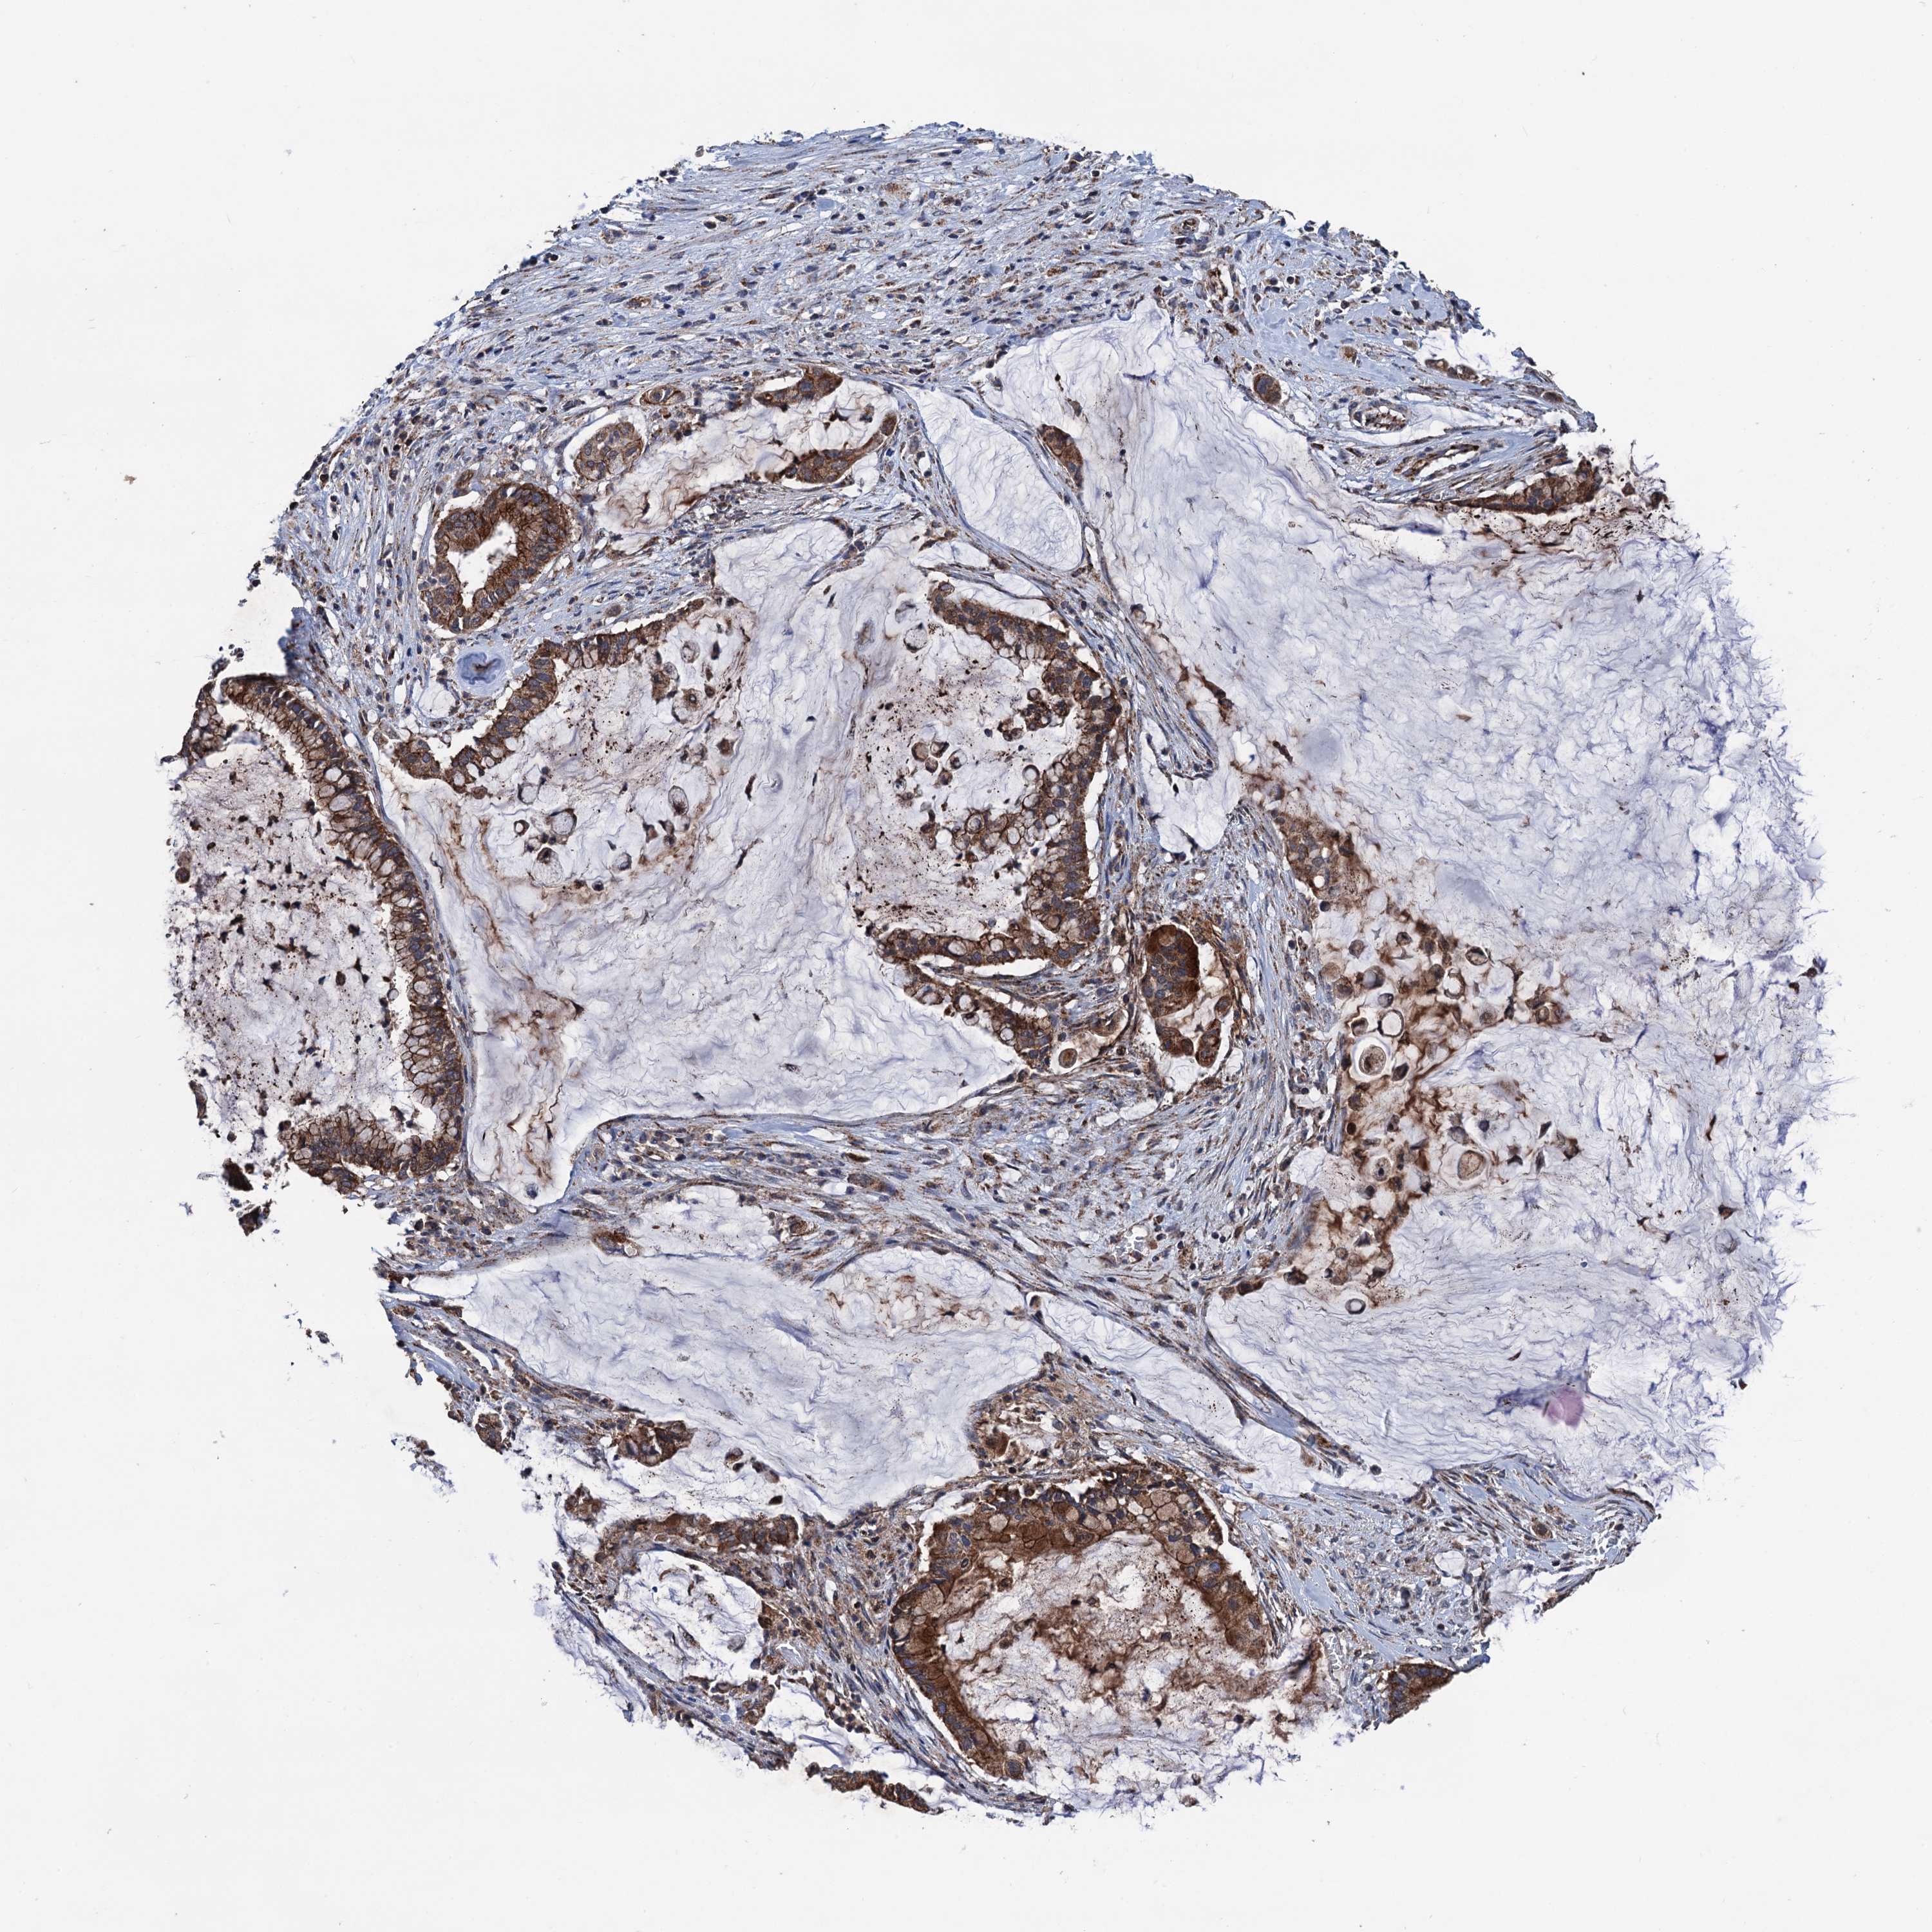

PANCREATIC CANCER - Protein expressioni

A mouse-over function shows sample information and annotation data. Click on an image to view it in a full screen mode. Samples can be filtered based on level of antibody staining by selecting one or several of the following categories: high, medium, low and not detected. The assay and annotation is described here.

Note that samples used for immunohistochemistry by the Human Protein Atlas do not correspond to samples in the TCGA dataset.

Antibody stainingi

Antibody staining in the annotated cell types in the current human tissue is reported as not detected, low, medium, or high, based on conventional immunohistochemistry profiling in selected tissues. This score is based on the combination of the staining intensity and fraction of stained cells.

Each image is clickable and will lead to virtual microscopy that enables deeper exploration of all samples and also displays staining intensity scores, fraction scores and subcellular localization as well as patient and tissue information for each sample.

Antibody HPA041423

Staining

High

Medium

Low

Not detected

Intensity

Strong

Moderate

Weak

Negative

Quantity

>75%

75%-25%

<25%

None

Location

Nuclear

Cytoplasmic/membranous

Cytoplasmic/membranous,nuclear

Adenocarcinoma, NOS